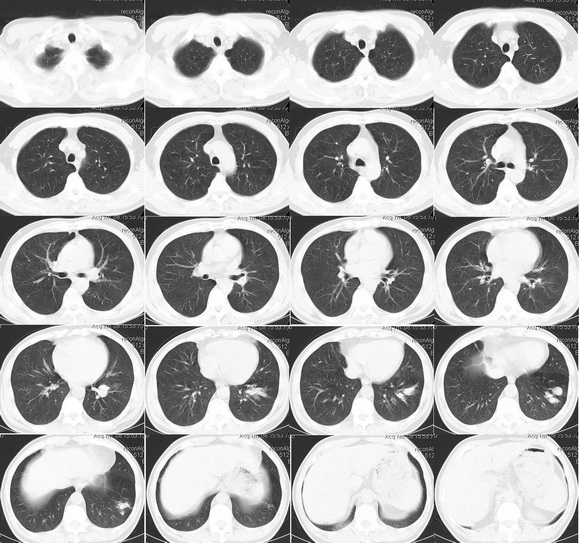

男性 45岁,咳嗽、咳血1月,曾用抗生素治疗10多天。

左下肺结节及肺门结节,增强延时似强化,周围性肺ca?机化性肺炎,建议支纤镜,穿刺

左肺下叶结节影,局部引流支气管增粗棒叉样改变,考虑真菌感染

不排除左肺下叶周围型肺癌并左下肺门区淋巴结转移可能。

考虑左肺下叶内基底段肺癌并支气管黏液栓形成或左肺门区淋巴结压迫支气管引起综合征.

考虑左肺下叶内基底段肺癌

还是这句话:炎症、结核、肿瘤逐样排除。病灶位于下叶,周围没有卫星及纤维条索灶,首先排除结核。

考虑左肺下叶内基底段肺癌并支气管黏液栓形成可能;建议随访复查。纤支镜未刷见癌细胞对于否定肺癌参考价值不大。

要看病人既往史,咳嗽时间的长短,咯血量的多少;倾向于考虑为支气管扩张(粘液栓)